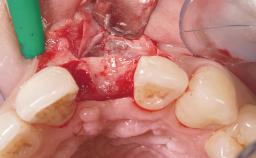

Immediate Flapless Placement of an Implant in a Maxillary Right Lateral Incisor Site

This 43-year-old male patient, a non-smoker, came to our practice because of a fracture of tooth 12 caused by a bicycle accident. Due to the combined para- and infrabony crown and root fracture, tooth extraction, and subsequent implant placement were suggested to the patient as the therapy of choice. The patient had high esthetic expectations with regard to the treatment outcome and asked for an immediate fixed provisional restoration. His individual esthetic risk profile summed up to a medium esthetic risk.

Soft Tissue Contour and Volume Ideal

General SAC Modifiers

Oral Hygiene and Compliance Good